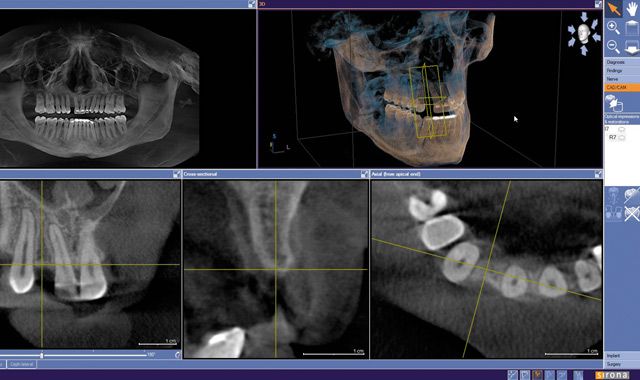

Fig. 08 Integrated implant treatment planning software allows the clinician to virtually plan implant placement in 3D.

Fig. 09 A cross-sectional image showing the integrated CAD/CAM virtual restoration with the planned implant.

Fig. 10 A volumetric analysis of comprehensive implant planning.